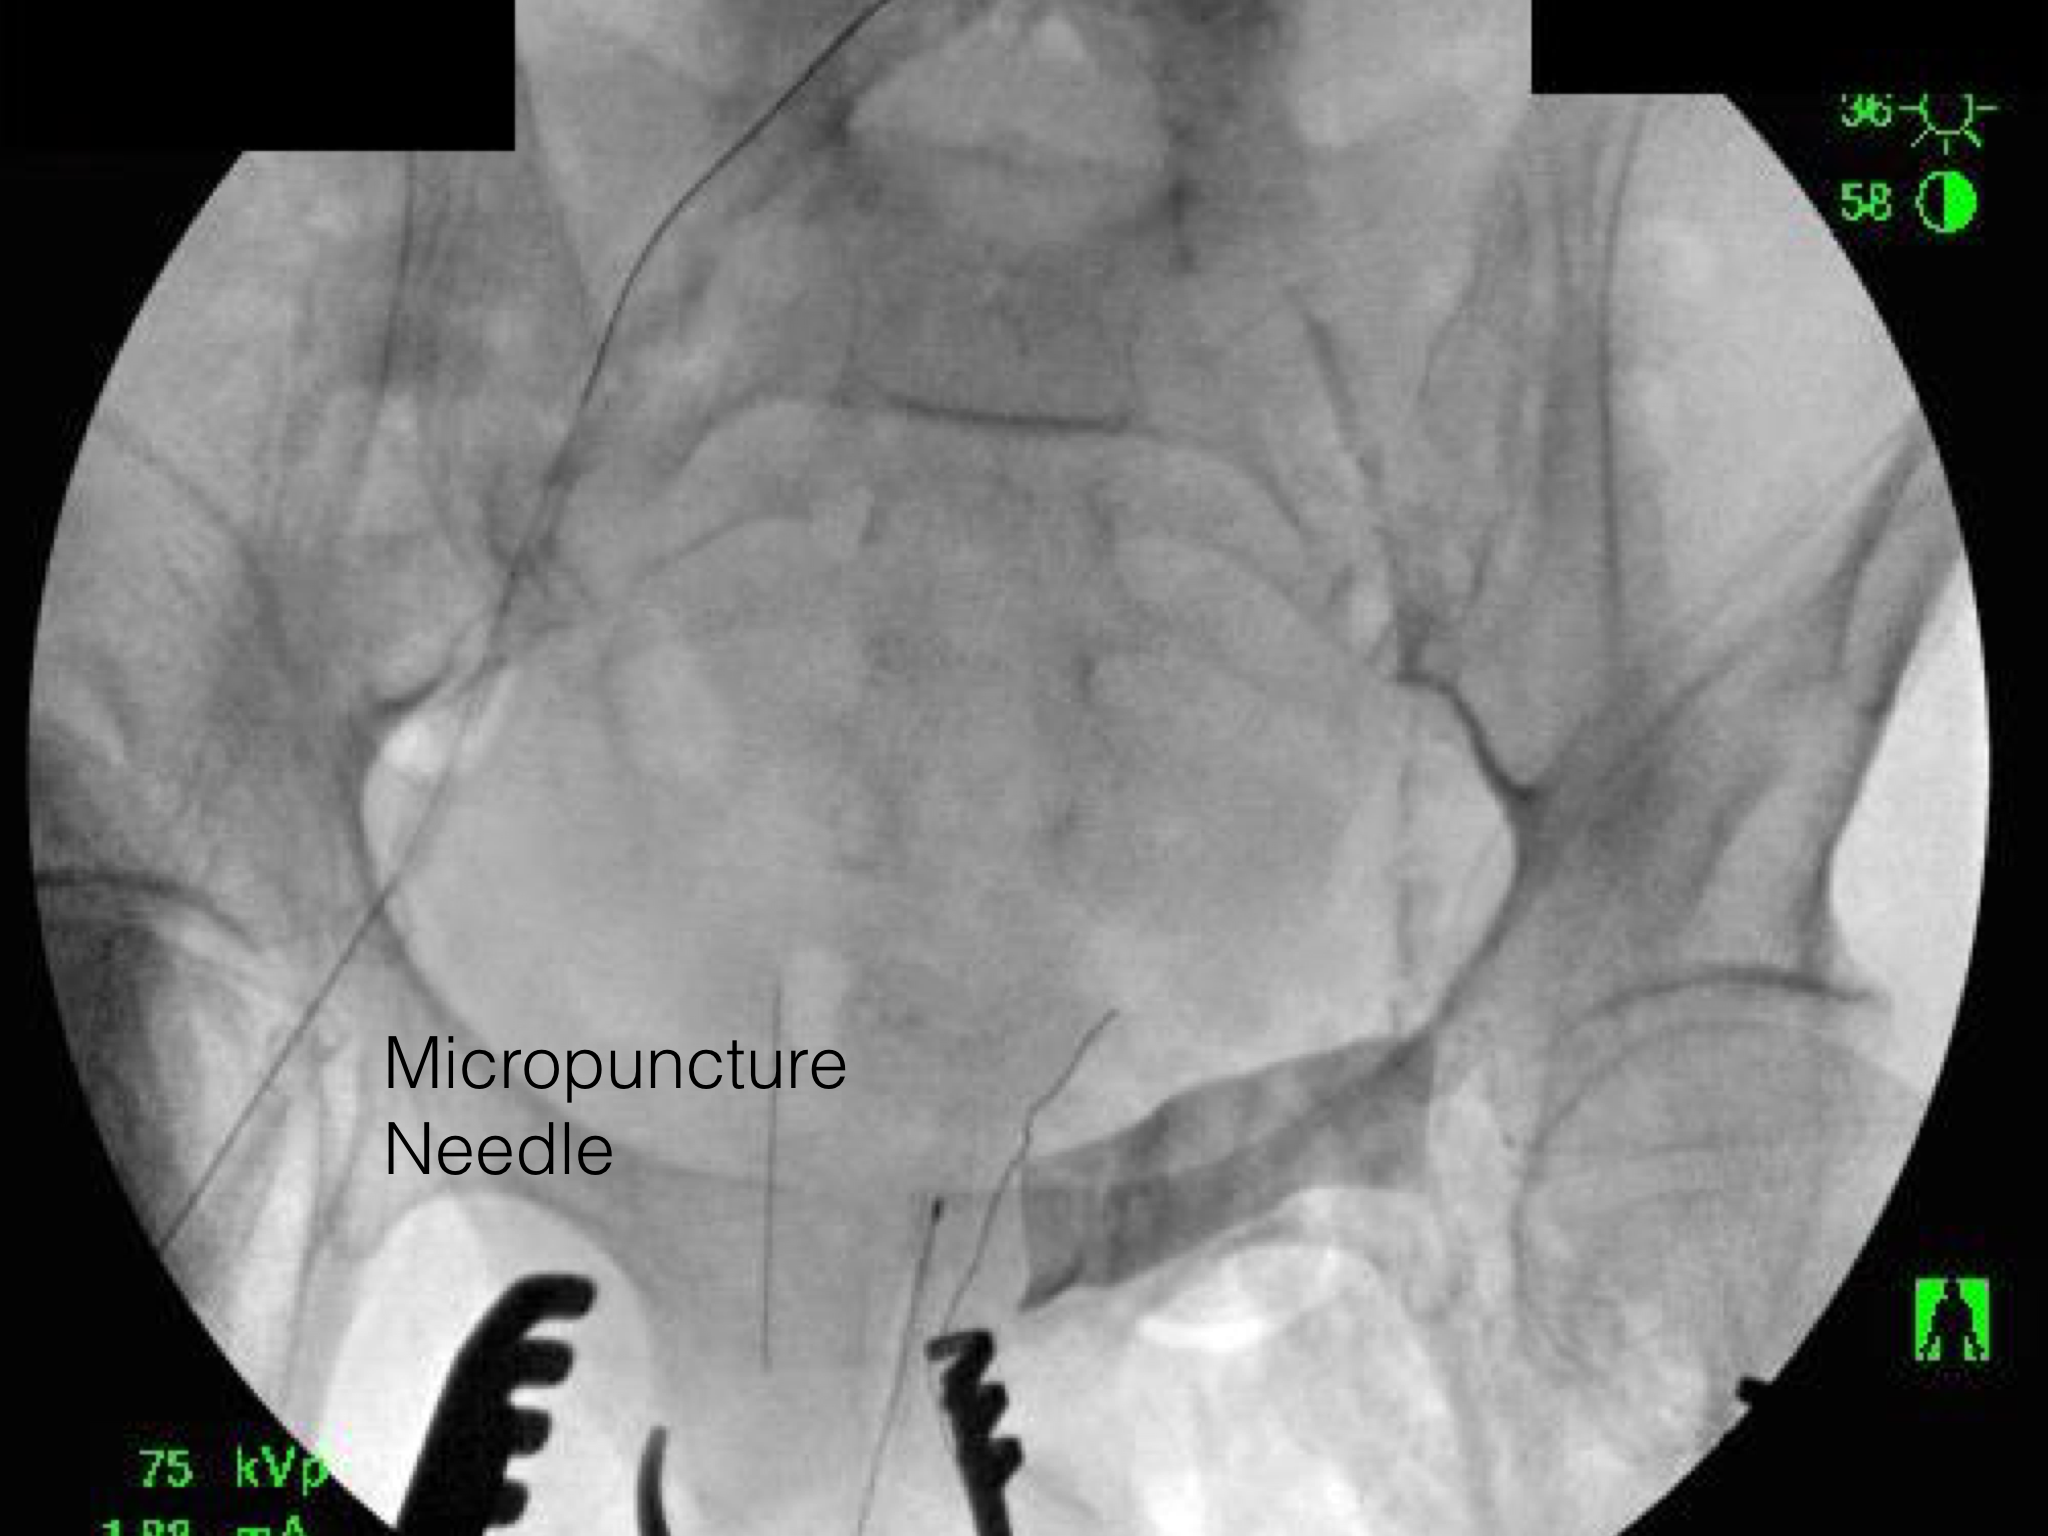

The patient’s thrombotic plaque went up to the renal origins and needed to be endarterectomized, but embarking on a renal endarterectomy adds potentially harmful renal ischemia time. Therefore, through the vertical aortotomy, I was able to get a clean end point to the aortic thromboendarterectomy and position a stent in the renal orifice and deploy it.

Once the stent was deployed, the aorta was partially closed primarily to allow the clamp to be moved below the renal arteries. This all took less than ten minutes of ischemia time. The aortic graft was then sewn end to side to the remaining aortotomy.